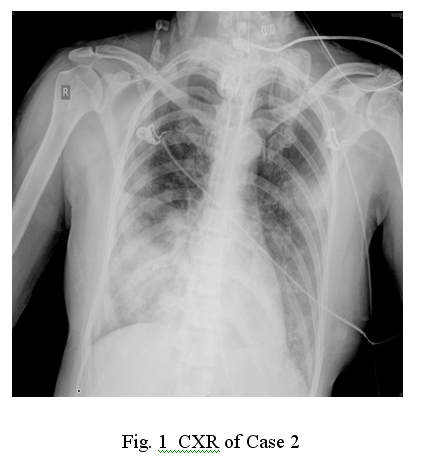

With her persistent high fever, she was transferred to our medical ward on 15/7/09 at around 9 pm. Her SaO2 was only 85% upon the transfer. Intravenous Amoxycillin- Clavulanate was switched to Cefepime empirically but her condition did not improve, and she was transferred to ICU subsequently on 16/7/09. Her SaO2 dropped to 90% while she was on 4 L/min of oxygen. ABG showed type I respiratory failure. Repeated WBC was normal with persistent lymphopenia while the liver and renal function tests were normal. CK and LDH levels were mildly elevated to 261 and 341 IU/L respectively and the first CRP was 202mg/L. Blood for HIV was negative. Repeated CXR showed marked increase of consolidative changes over both lower zones and HRCT confirmed wide spread airspace shadowing over corresponding areas. (Fig.1)

Her condition continued to deteriorate and eventually required intubation and mechanical ventilation with PEEP. Bronchoscopy was performed with bronchial lavage on 17/7/09. RT PCR for swine flu was positive for both tracheal and bronchial aspirates. Tamiflu at 75mg BD was initiated and continued for 10 days.